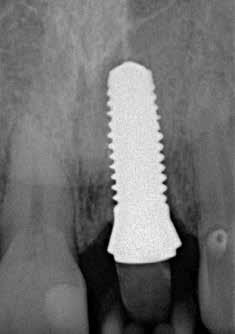

Egy harmincéves hölgypáciens jelentkezett a klinikánkon elsősegélyért egy törött bal felső középső metszőfoggal (2�1-es fog)� A törés nem volt látható (1. ábra), de hamarosan a korona levált a fogról (2. ábra)� Egy hagyományos röntgenfelvétel alapján (3. ábra) úgy döntöttünk a pácienssel együtt, hogy a fogat eltávolítjuk, és a helyére azonnal behelyezünk egy 13 mm hosszú és 4,5 mm átmérőjű kétrészes Patent implantátumot (4. ábra)� Emellett egy azonnali terheléses protokoll mellett döntöttünk, aminél egy ideiglenes korona kerül az implantátumra ugyanabban az ülésben [3, 6]� Három alternatív kezelést vettünk fontolóra:

3. ábra: Kiindulási állapot, röntgenfelvétel. 4. ábra: 13 x 4,5 mm-es Patent implantátum. 5. ábra: A gyökér extraktor.